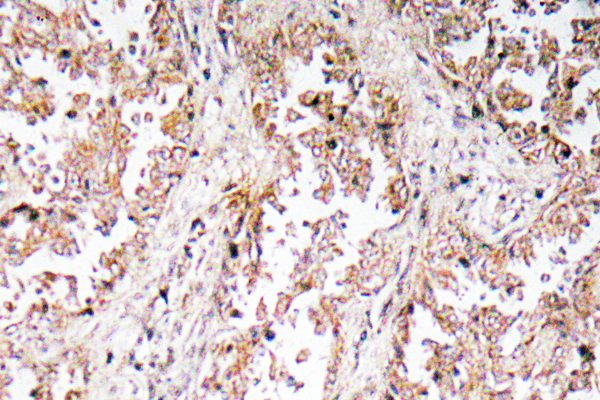

Anti-ABCD4 AntibodyA97754

ApplicationsWestern Blot, ELISA, ImmunoHistoChemistry

ReactivityHuman, Mouse